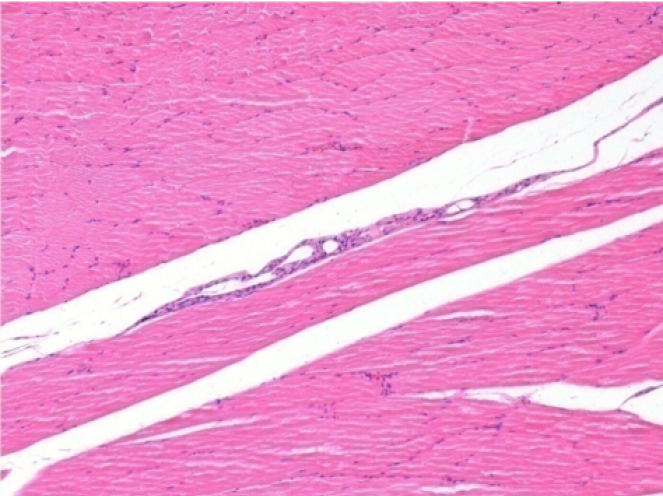

09

7 months after Endopeel Injection

7 months (D210)after Endopeel IM Injection 0.1ml in the right pretibial muscle.

Complete Restitutio ad integrum after 7 months

L : Control-100xD210

R:100xD210

L :Control 50xD210

R50X-D210